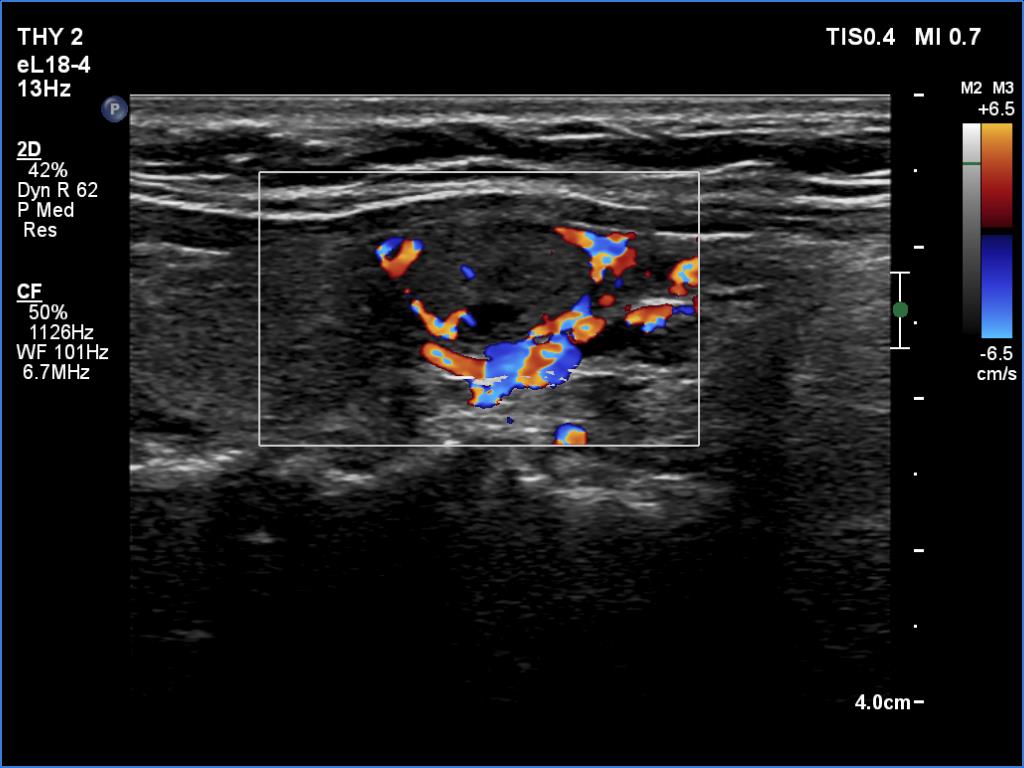

Examination a year after the first visit (third row of images):

Clinical presentation: The patient had no complaints.

Palpation: no abnormality.

Laboratory tests: TSH 2.05 mIU/L, FT4 13.7 pM/L.

Ultrasonography: The ultrasound pattern has normalized. There was a moderately hypoechoic nodule in the right lobe while a cystic lesion in the left one.

Cytology of the right nodule resulted in benign colloid goiter.

Suggestion. Follow-up in two years.